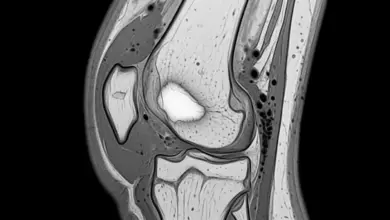

- A tomografia computadorizada costuma ser o exame mais sensível para visualizar o nicho tumoral e localizar a lesão com precisão.

- A ressonância magnética complementa a avaliação, principalmente para identificar edema ósseo e sinais de inflamação sinovial, algo mais relevante quando existe envolvimento articular.